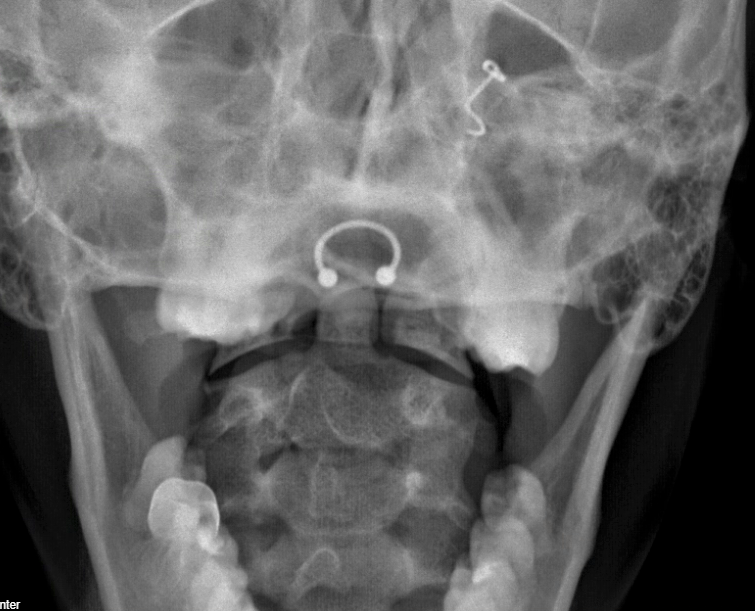

A close look at the odontoid view showed something concerning.

There is a line at the base of the dens concerning for a type II fracture, which would be considered unstable.

Something didn’t fit, though. This patient’s wreck had been a week ago. Also, the line feels a little “too clean”. I looked at it with the residents, but the answer was not clear to them. Do you see any issues?